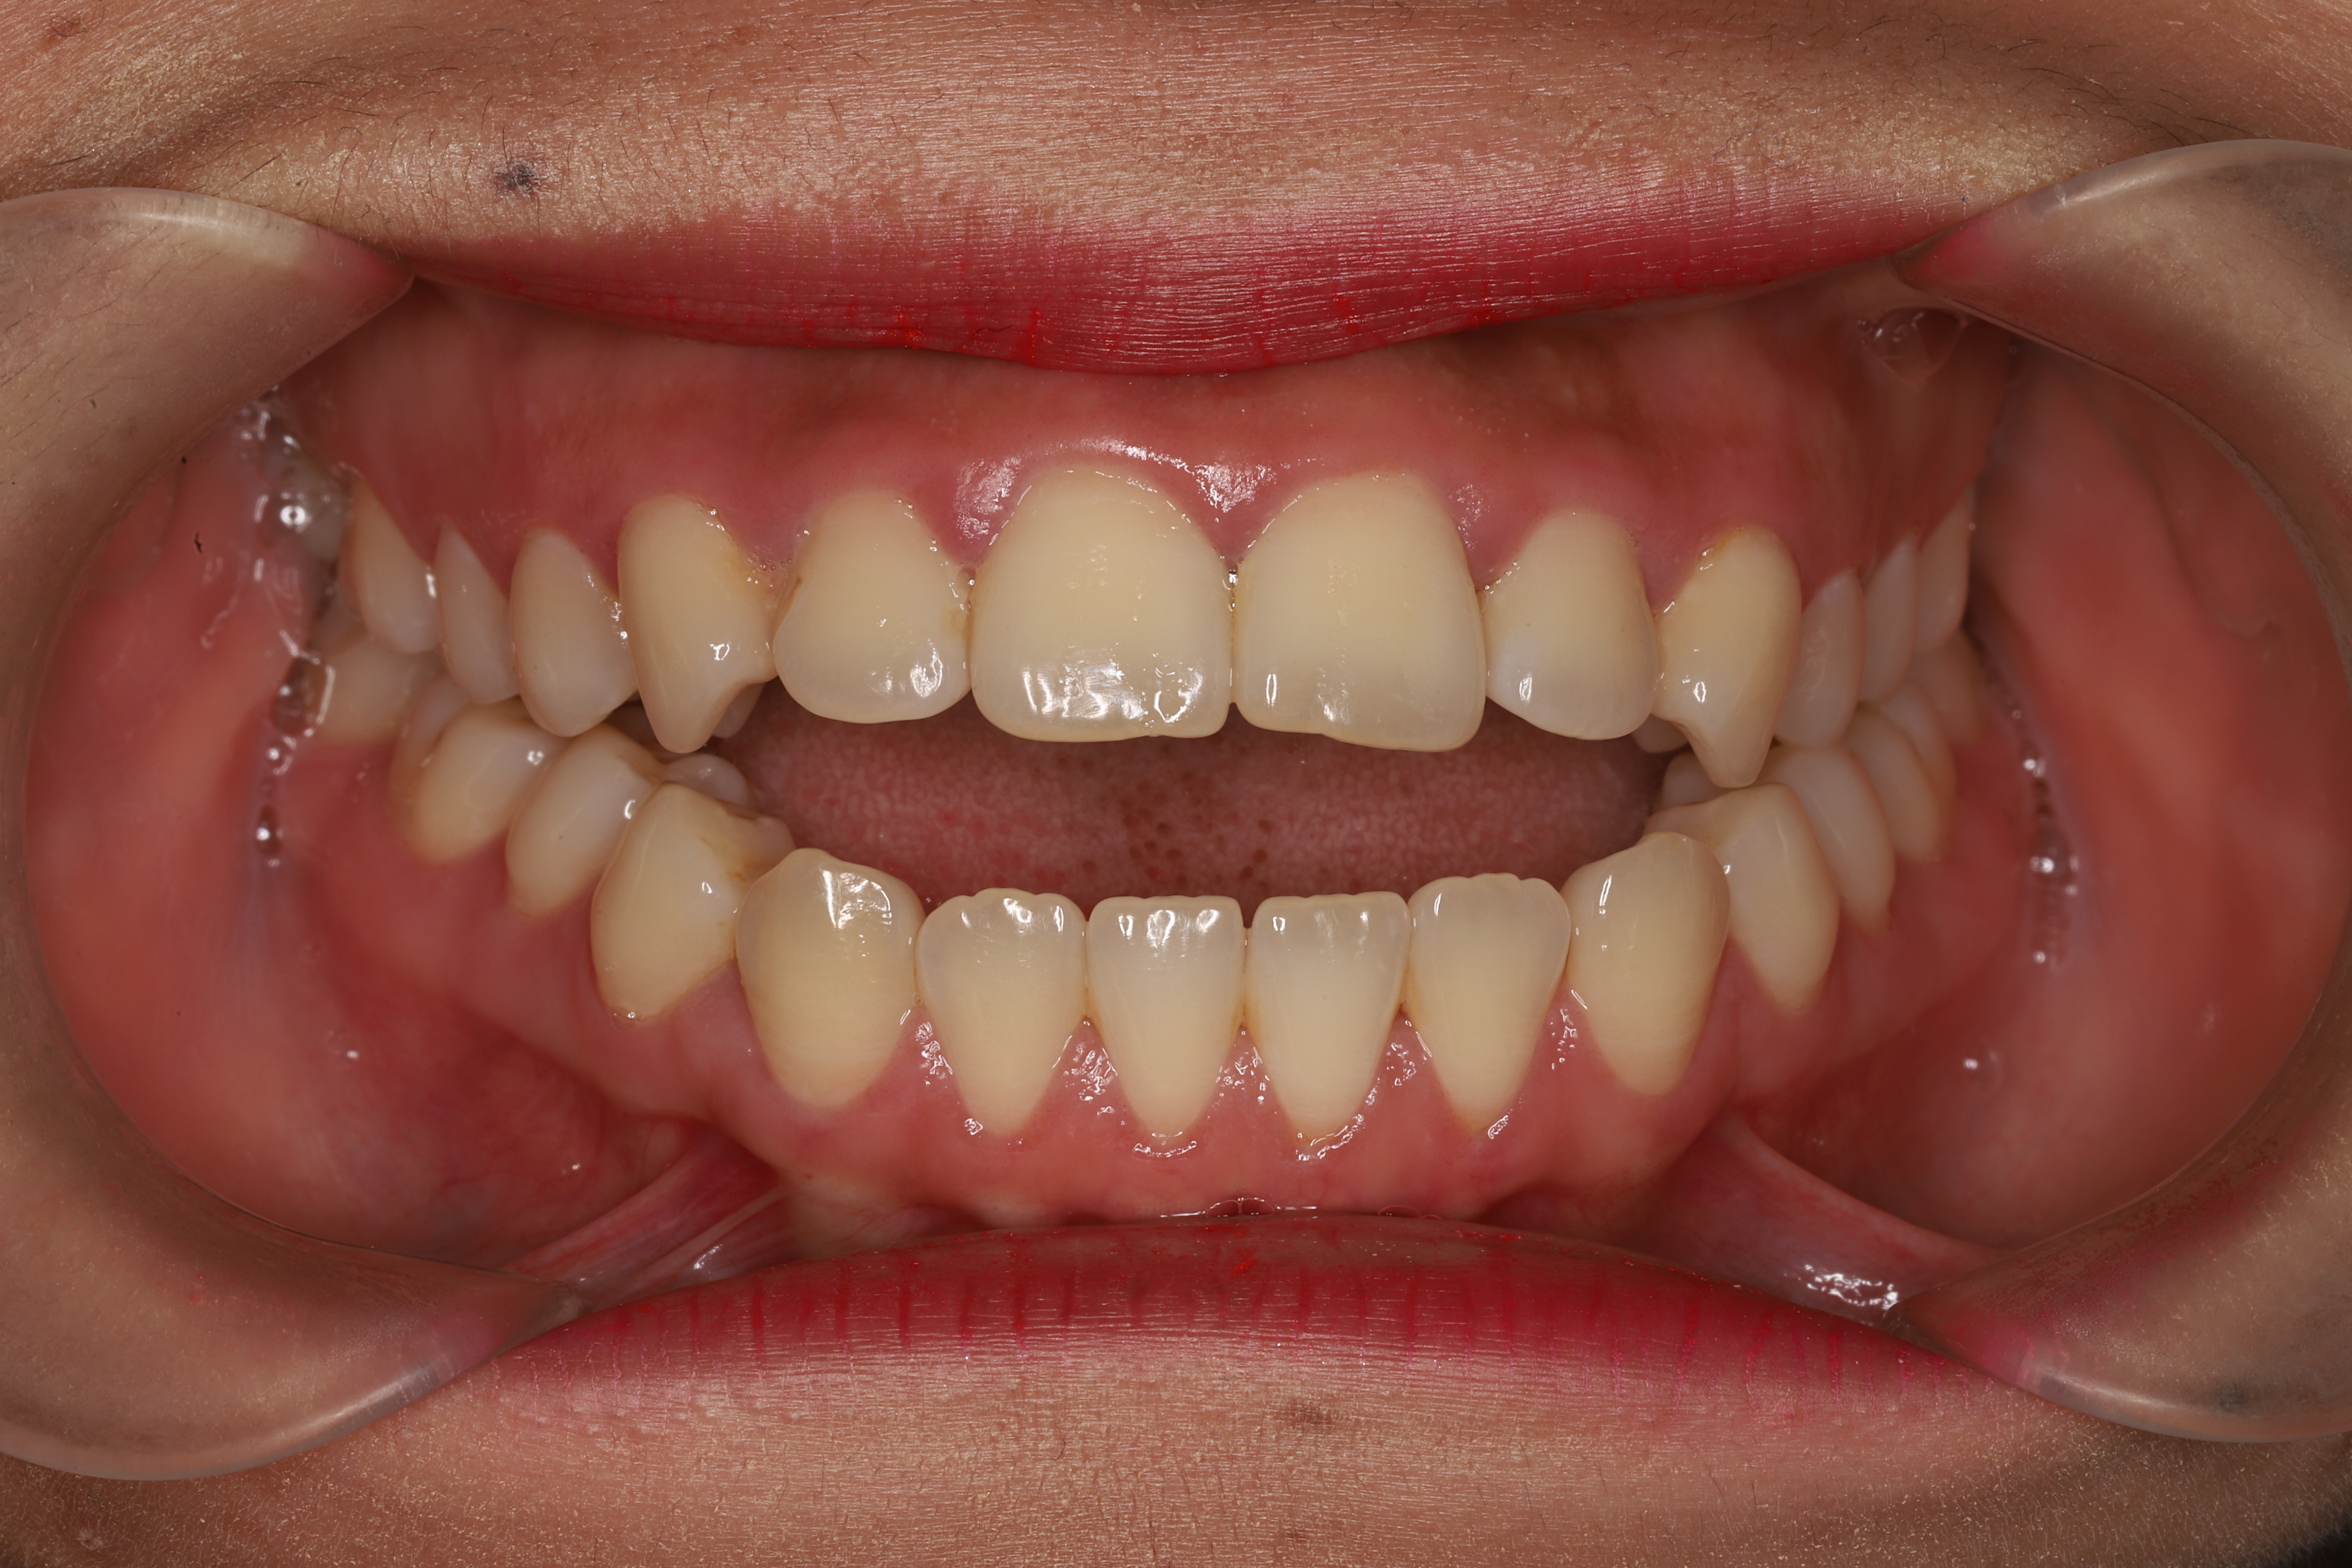

关于儿童牙齿矫正那些事(图5)

牙齿拥挤

1-24061G6112Q45.JPG

龅牙

如果存在以上任意一种情况,那么都是属于牙齿排列不整齐,是需要及时进行干预和矫正的。大多数人认为牙齿不齐只会影响美观,所以很多家长不以为然,其实牙齿不齐对人体的危害远不止于此,它不仅仅影响我们的外貌,对健康也有很大的影响。那么牙齿不齐具体有哪些危害呢?我们一起来了解一下吧!